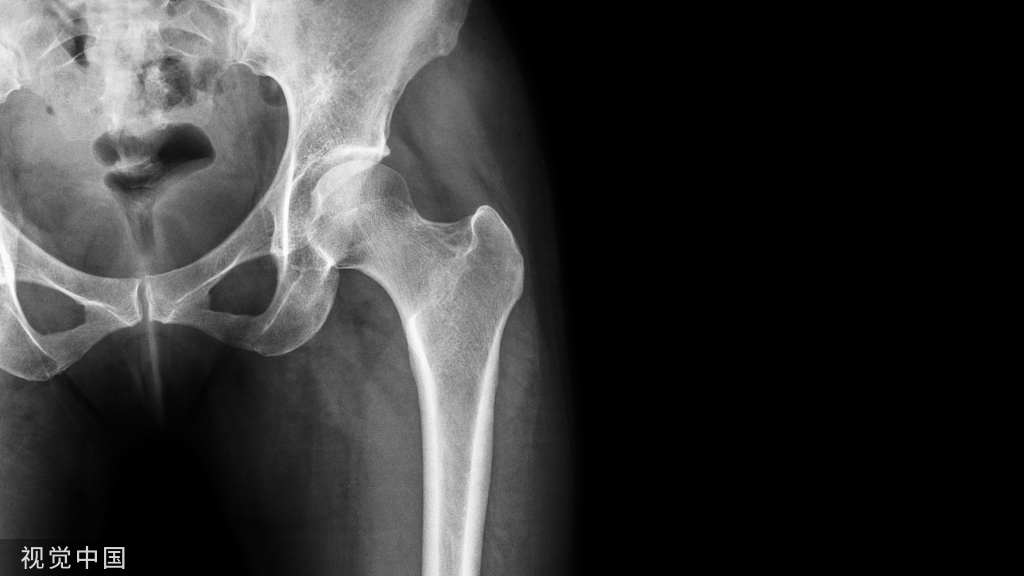

L3-L4左侧复发椎间盘突出